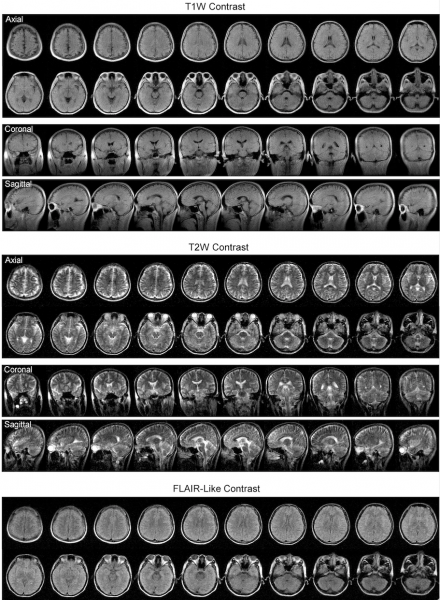

他的團隊與瑪麗醫院神經外科的梁嘉傑教授和其他醫生合作,透過將ULF磁力共振影像掃瞄儀與標準 3 特斯拉磁力共振影像掃瞄儀獲得的影像進行比較,成功驗證使用 ULF磁力共振影像掃瞄儀得出來的結果。儘管影像的清晰度和解像度不及精確診斷所要求的程度,他們已能區別出大部分相同的病理,包括中風和腫瘤結果。